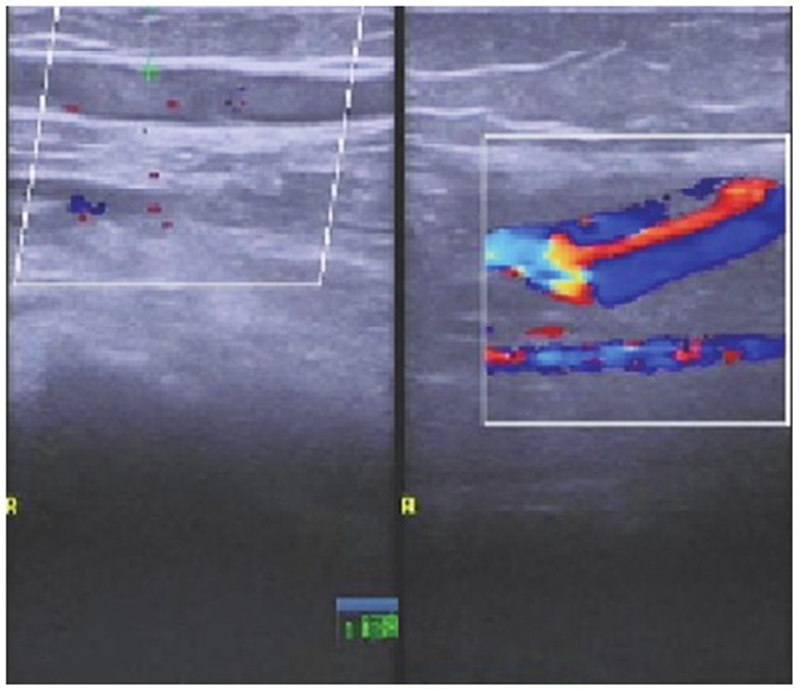

术后第1天复查下肢血管彩超及实验室检查凝血功能,发现腘动脉血栓形成及凝血功能异常(图4~5),患者未诉 不适。体检发现足背动脉搏动较对侧弱,皮温略低,末梢血氧饱和度90%。请显微外科及心血管内科会诊后,心血管内科建议切开取栓,将病情告知患者及家属后行急诊取栓术。术中可见腘动脉分叉近端约2cm大小的半月板缝合袢将腘动脉捆扎,但仍有血流通过(图6),切开血管,取出血栓,取出半月板缝合袢,松开止血带,见血流好,在显微镜下修复腘动脉,再次松开止血带,见动脉搏动良好,无漏血,足背动脉搏动好,末梢血氧饱和度99%,手术完毕。患者术后第1天开始主动活动,双侧皮温一致,未诉患肢疼痛,复查右下肢动静脉彩超示右侧动静脉血流通畅(图7),术后24个月随访患者右下肢活动功能良好,双下肢无明显肿胀,双侧皮温一致,小腿腿围基本一致,患者McMurray征阴性,前抽屉试验阴性,膝关节稳定性良好,活动度良好。

图4 术后 第1天彩超可见一条索状与心率一致的搏动性阴影(红色虚线区 域),提示右侧腘动脉血流减缓

图7 右侧腘窝处皮下血管内低回声点提示浅表静脉早期血栓形成